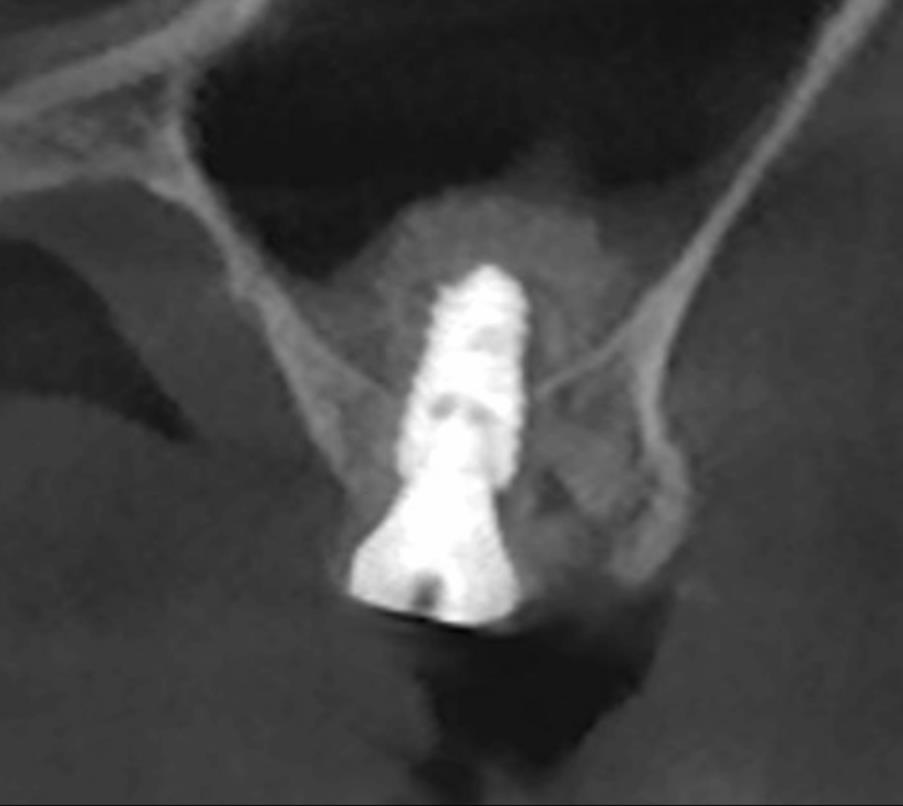

수술 전 CT – 뼈 높이가 부족해 상악동 거상술 필요 소견

수술 후 CT – 상악동 뼈가 안전하게 거상된 모습